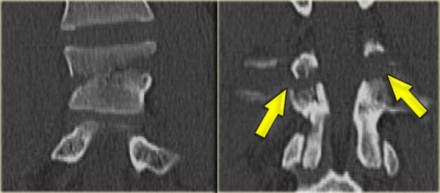

On the left images of a 21-year-old female who presented after sustaining a seatbelt type injury.

She had an exploratory laparotomy for repair of a ruptured duodenum.

There was no neurologic deficit.

First study the images, then continue reading.

What we see is a classic example of a chance fracture,

which is a three column injury with a horizontal orientation of the

fracture.

Continue with the CT-images.

What is unique about the Chance fracture is the

horizontal orientation, which is nicely demonstrated on the sagittal

reconstructions on the left.

Continue with the coronal reconstructions.

Also on the coronal reconstructions we can see the horizontal orientation of the fracture.

What type of circumstances results in a fracture of this type?

The classic mechanism of this injury is a lap-belt injury.

If you don't have an addtional shoulder belt, the body will fold over.